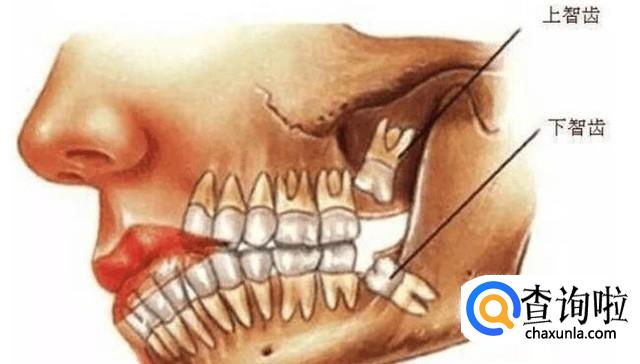

首先,长了智齿的话,如果智齿靠近我们的神经的话,那么这样的智齿是不能拔的,因为如果拔的话,一旦碰到神经的话,那么对我们的身体伤害是巨大的,一般医生也不会建议我们拔的,我们需要定期清理干净我们的智齿处。

其次,如果我们的智齿总是导致我们的嘴巴处发炎的话,那么这样的智齿往往是需要拔除的,因为总是发炎对身体的伤害也是比较大的,这时候是必须要拔的,拔除后,我们需要确保不感染才行。

之后,如果我们的支持长出来后,对我们的饮食等各方面都没有任何影响的话,那么这样的智齿是不需要拔的,拔的也没有多大用处的,我们只需要每天坚持刷牙,确保口腔干净即可。

最后,我们需要根据实际情况来确定是否需要拔掉智齿,如果智齿直接顶到另一颗牙齿生长的话,这样的智齿我们也是需要拔除的,不然我们的整体牙齿都会有一定的伤害,这是必须要拔的。